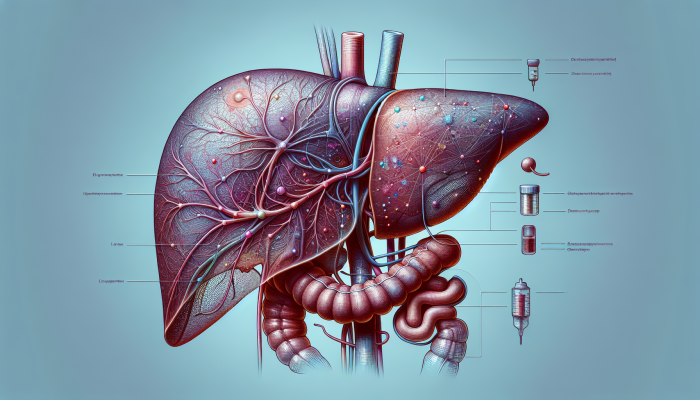

Understanding the essential role of the liver in maintaining our overall health is crucial for every person. Consistent monitoring through advanced liver blood tests in Tewkesbury is key to not only detecting potential health issues early but also to enhancing our comprehension of liver health. The liver is responsible for a range of crucial functions, which include detoxification, metabolism, and protein synthesis. These processes are vital for sustaining life and ensuring optimal physical health. By prioritising liver health, individuals can safeguard their wellbeing and avert serious health complications in the future.

Regular monitoring of liver function through consistent testing is a cornerstone of preventative healthcare. The liver can sustain considerable damage before symptoms manifest, which underscores the necessity of routine checks to identify conditions such as hepatitis, cirrhosis, or fatty liver disease early on. The profound benefits of early detection cannot be overstated—swift intervention can be the deciding factor between managing a health issue effectively and facing life-threatening complications. Frequent testing empowers individuals to take control of their health by identifying risks before they escalate into serious conditions.

Many individuals may not notice symptoms until their liver is substantially damaged, which is alarming considering the rising rates of liver disease in the UK, largely attributed to increasing levels of obesity and alcohol consumption. Regular testing can reveal concerning biomarkers, such as elevated liver enzymes, enabling timely intervention before severe complications develop. Ultimately, establishing a routine of regular testing fosters a proactive approach to personal health management, ensuring that individuals stay informed and empowered regarding their liver health.

Advanced liver blood tests offer a comprehensive analysis of liver health, employing sophisticated technology to detect abnormalities that standard tests may overlook. These tests typically evaluate specific enzymes and proteins that reflect liver functionality, providing clearer insights into potential liver diseases and conditions. This thorough approach is crucial in contemporary healthcare, ensuring precise diagnoses and effective management strategies.

Furthermore, advanced testing can distinguish between various liver conditions such as alcoholic liver disease and non-alcoholic fatty liver disease, allowing for tailored treatment approaches that cater to the unique needs of each patient. The accuracy and depth of these tests empower healthcare providers to closely monitor liver health, leading to improved outcomes for individuals. Embracing advancements in testing methodologies is of utmost importance; by leveraging new technologies, both patients and healthcare providers can collaborate effectively to manage liver health and enhance overall wellbeing.